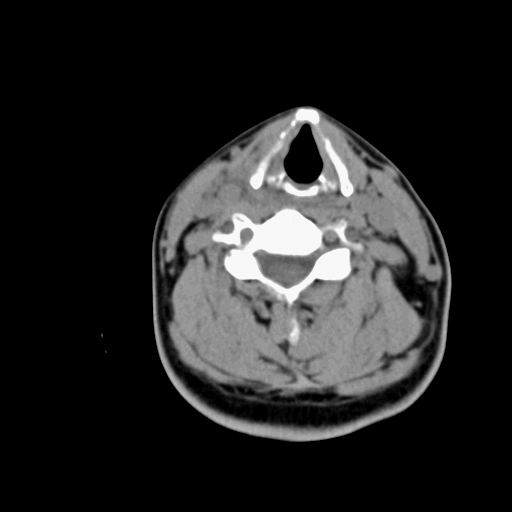

1.甲状腺ca:中年妇女好发,病例分型,乳头状、滤泡状、未分化癌及髓样癌四种。

ct表现:形态不规则的软组织密度肿块,可累及部分或大部分甲状腺组织,密度不均,可坏死、囊变、钙化,增强病灶呈不均匀强化,有局部侵犯或转移时可有颈部淋巴结肿大。

2.甲状腺腺瘤;常见的良性肿瘤,病理分型:滤泡状腺瘤、乳头状囊性腺瘤,以前者多见,腺瘤周围有完整的包膜,患者大多为中青年女性,大部分无任何临床症状。

ct表现肿瘤呈稍低密度结节状肿块,边缘光整、锐利病灶均匀强化,少数腺瘤可有钙化。